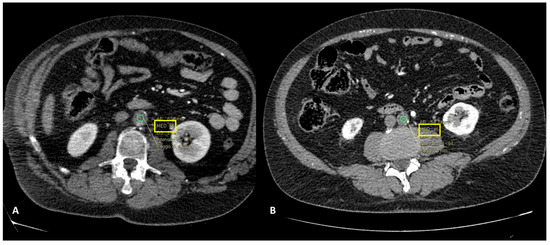

- In one case (9.1%), hypoperfusion of the intestinal loops was evidenced due to extensive thrombosis of the superior mesenteric artery (Figure 5); this patient was the one with predominant abdominal pain symptoms.